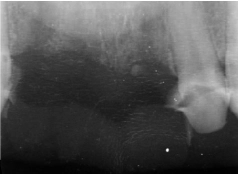

• Tình trạng răng trước đây:Từng bọc răng sứ bị hư, mất răng lâu năm

• Bác sĩ chỉ định:Cấy ghép 2 trụ Implant

• Implant sử dụng:Implant Dentium Hàn Quốc

• Răng sứ sử dụng:Răng sứ Titan Mỹ